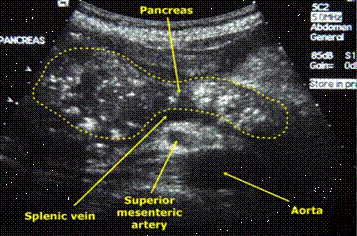

Менее очевидна диагностика рака поджелудочной

железы, так как этот вид опухоли имеет изоденсивную плотность и при

внутривенном контрастировании меняет свои свойства одинаково с непораженной

паренхимой органа. При раке головки поджелудочной железы обнаруживаются

признаки механической желтухи в виде расширения внутри- и внепеченочных желчных

протоков, застойного желчного пузыря, блока холедоха на уровне опухоли.

Дополнительными симптомами опухоли в любой части железы являются ее объемное

увеличение, отсутствие дифференциации с окружающими тканями, признаки

прорастания в соседние органы.

УЗИ пожделудочной железы